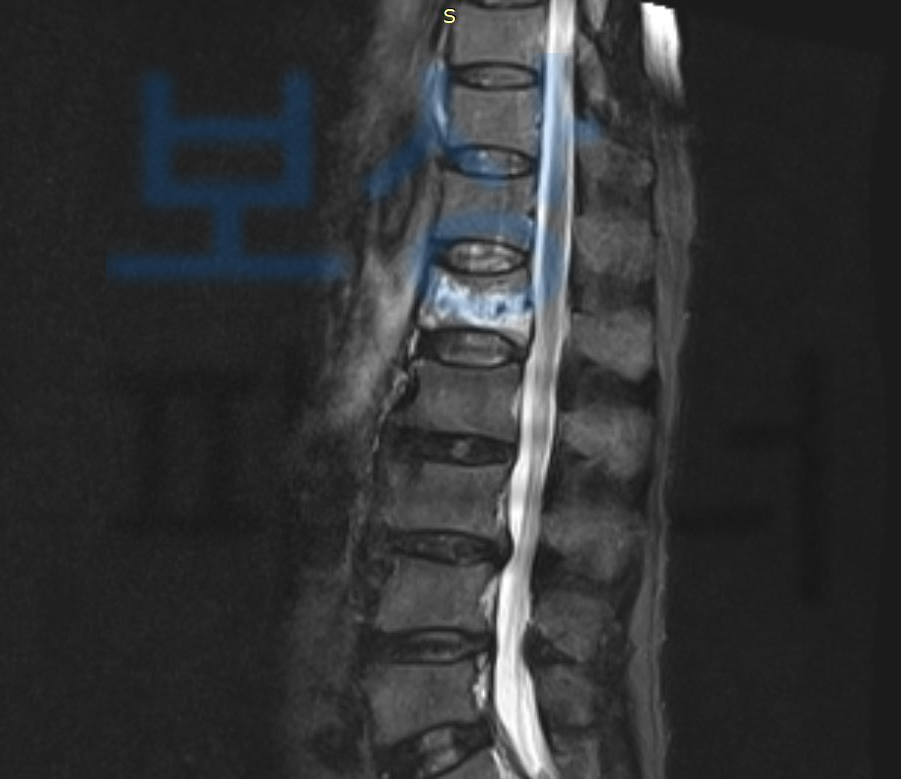

사고 이후 최@@님은 극심한 허리 통증을 호소하셨고 병원에 내원하여 정밀검사를 한 결과

요추1번골절 S32020 진단받아 허리 보호대 (TLSO보조기) 착용하며 요양하셔야 했는데요, 문제는 골절된 척추체가 시간이 경과하며 찌그러지듯 심하게 주저앉게 되었고 결국척추체의 공간을 확보한 후 의료용 시멘트를 주입하여 굳히는 골시멘트술을 받으셔야 했습니다.

하지만 시간이 결과함에도 요추1번골절 호전이 안되었고 결국 척추유합술 까지 받게 되었죠.